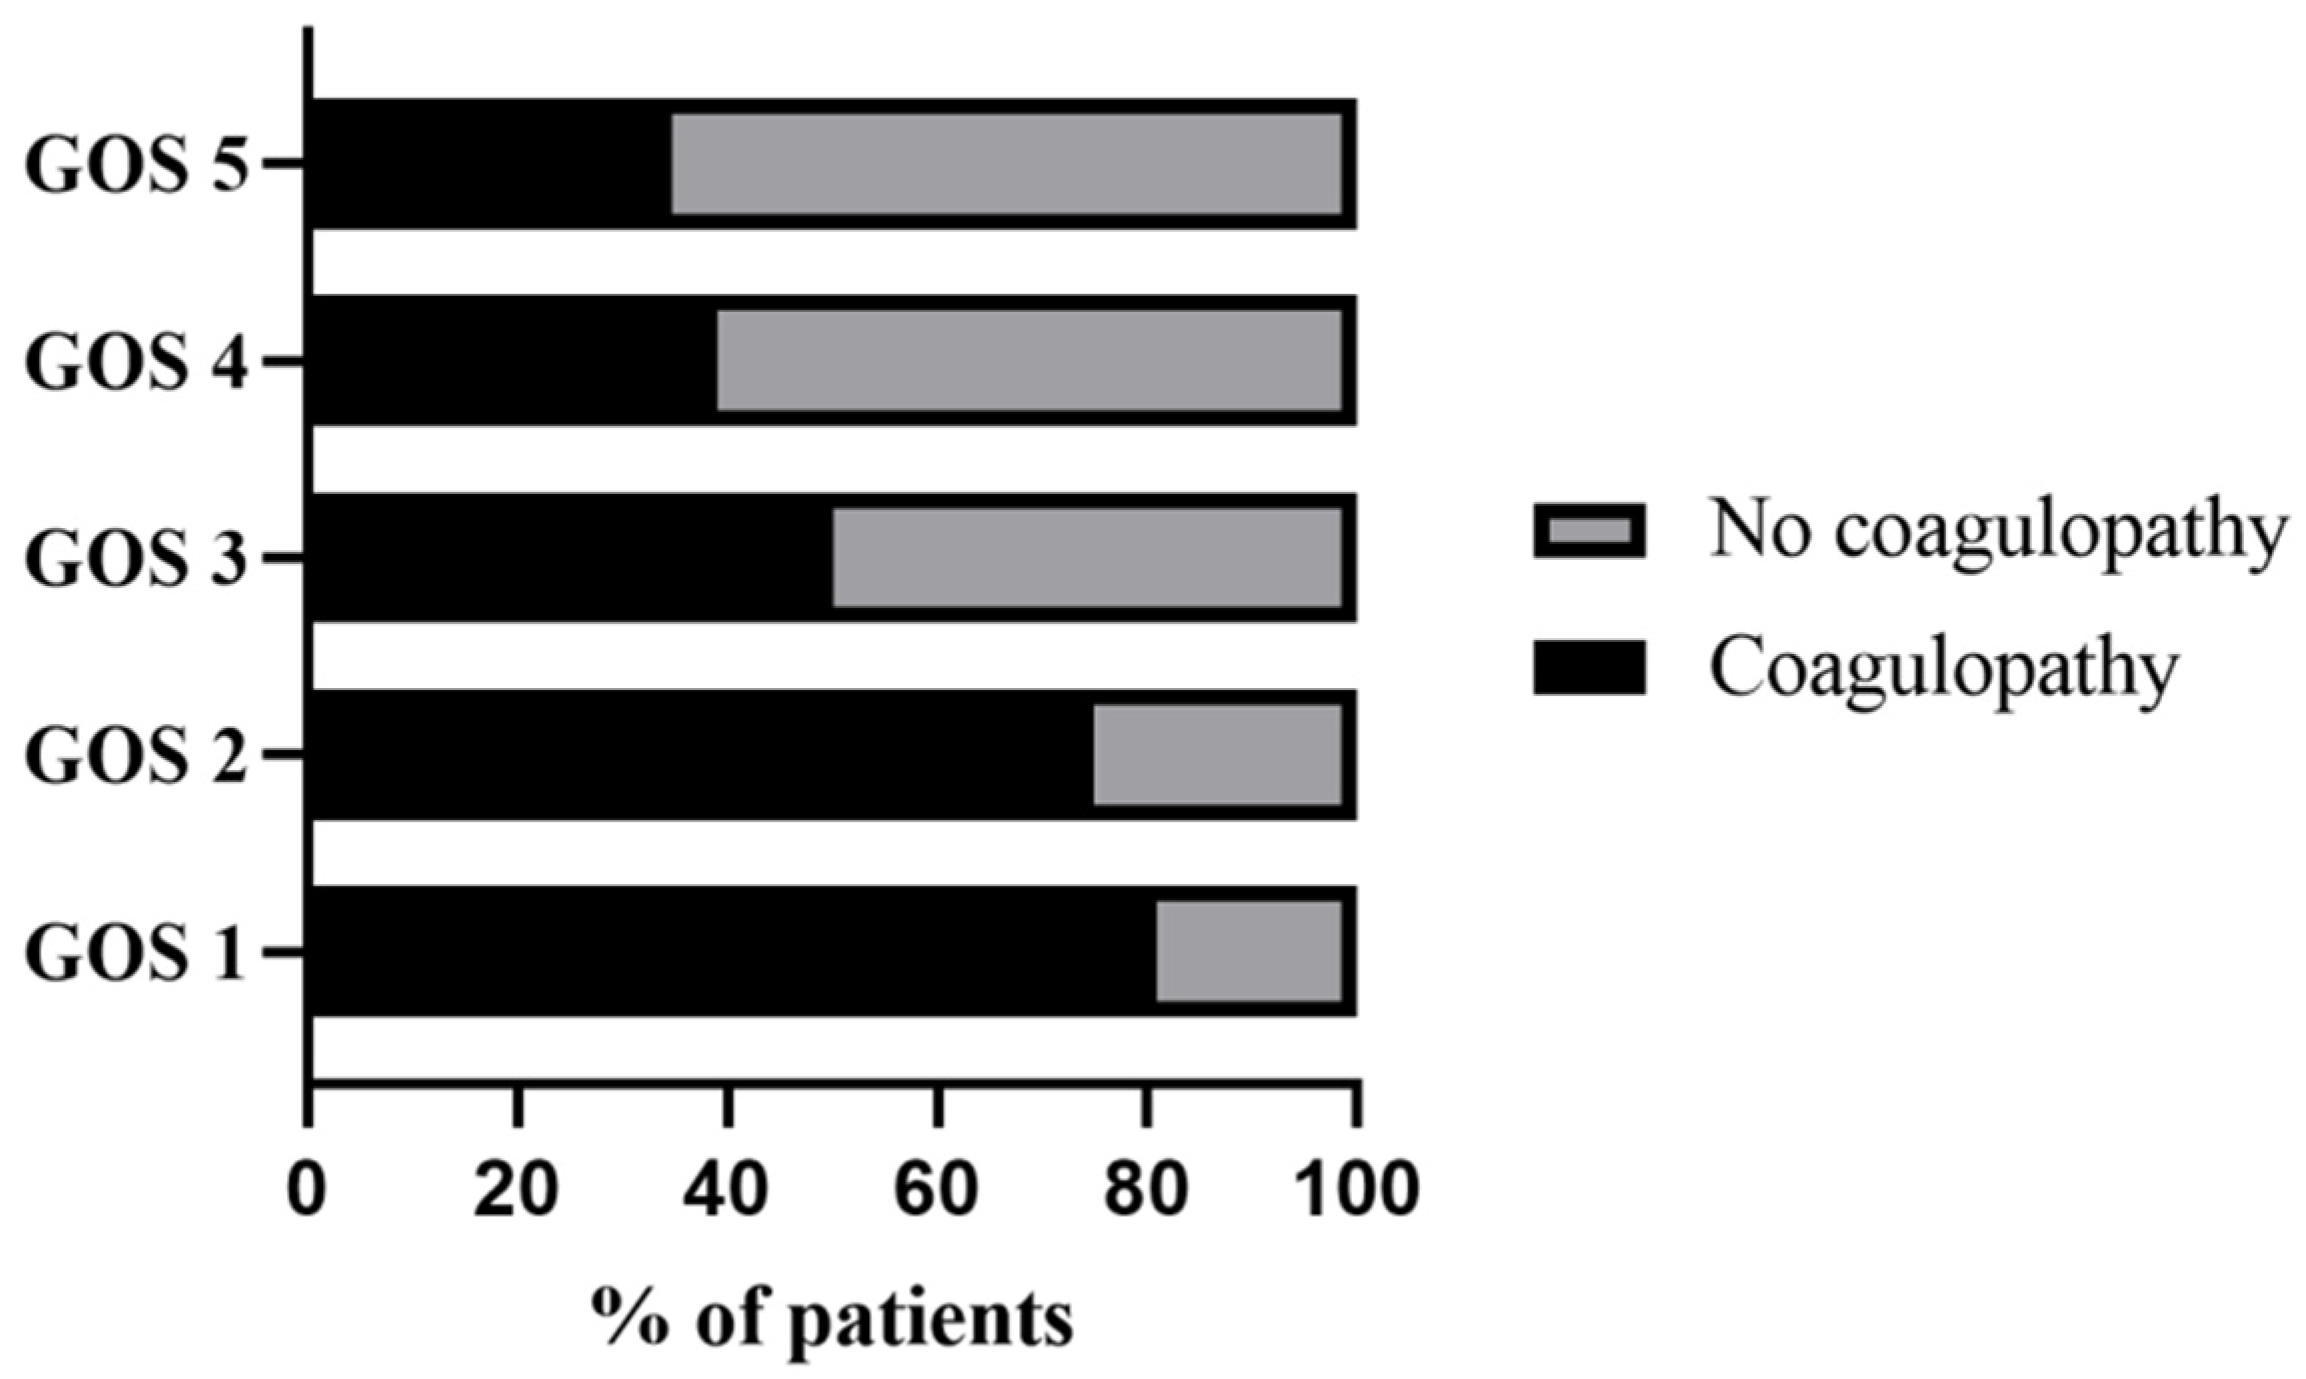

7.5. Outcomes Associated with Coagulopathy

| All Patients | Coagulopathy | No Coagulopathy | p Value | |

|---|---|---|---|---|

| Favorable functional outcome (GOS score of 4–5) | 97 (73.5) | 21 (45.7) | 76 (88.4) | <0.001 |

| Unfavorable functional outcome (GOS score of 1–3) | 35 (26.5) | 25 (54.3) | 10 (11.6) |